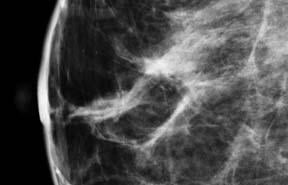

April 3, 2012 — Breast cancer patients whose treatment includes radiation therapy are at higher risk of complications after implant-based breast reconstruction, reports a study in the April issue of Plastic and Reconstructive Surgery, the medical journal of the American Society of Plastic Surgeons (ASPS).

The researchers looked at how radiation affected complication rates in 194 breast cancer patients undergoing two-stage, implant-based breast reconstruction after mastectomy. About 12 percent of reconstructions were done on women undergoing radiation therapy before mastectomy, and six percent in women who received radiation after mastectomy.

The results confirmed an increased complication rate in women undergoing radiation therapy, whether before or after mastectomy. In both radiation groups, the complication rate during reconstruction was over 40 percent, compared to 14 percent for women who did not receive radiation.